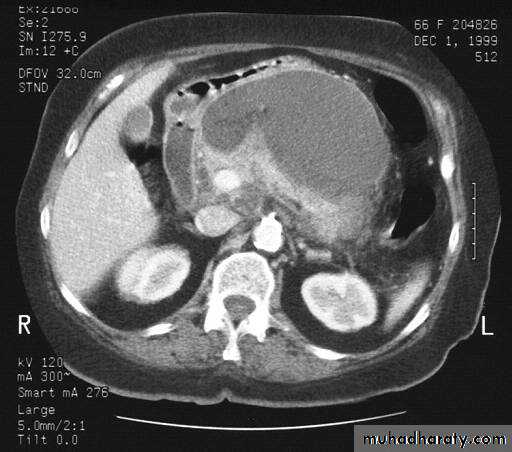

Secondary metastasis in the liver

Multiple rounded hypo density areas of different density , shape & different size .

Pattern of enhancement is either uniform , target or bulls eye pattern .

Hepato megaly .

Secondary metastasis within the liver